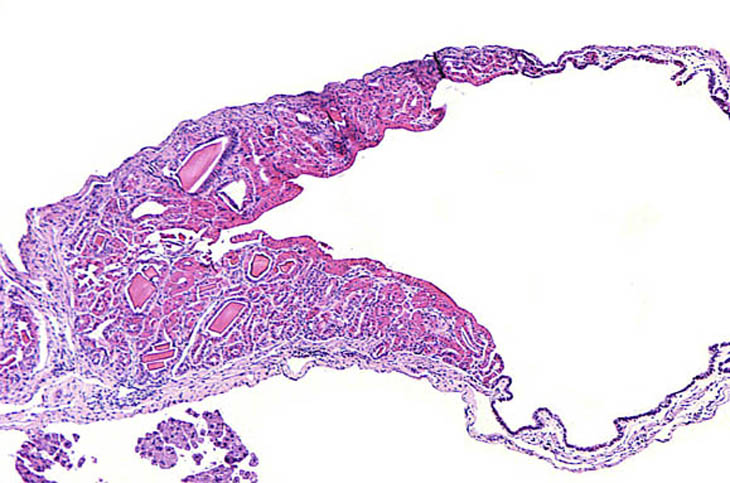

Eosinophilic crystalline inclusions and hyalin degeneration of epithelial cytoplasm in an adenomatous hyperplasia of the gallbladder. High magnification shows the brightly eosinophilic hyalinized cytoplasm of the epithelial cells.